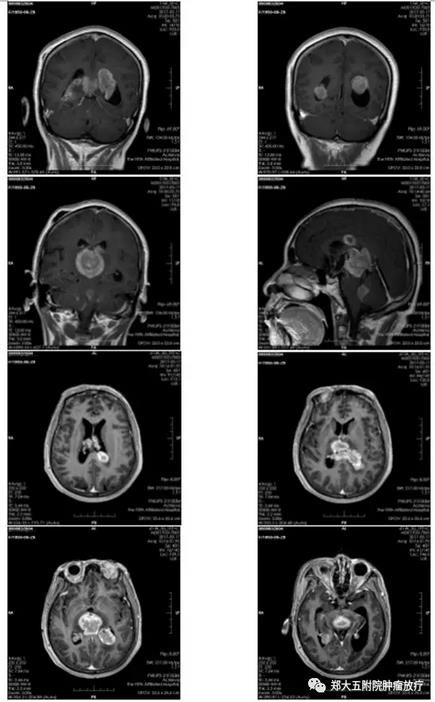

▲ 患者放疗前核磁共振图

然而,好景不长,2017年5月16日,王大妈因突发意识模糊再次来到郑州大学五附院,复查头部MRI提示颅内肿瘤较前明显增大,且病变波及到脑干,脑脊液循环受阻。经放疗科主任医师王晓瑜主任会诊考虑颅内多发占位,恶性淋巴瘤可能性大,不排除生殖细胞瘤。当时病人神志模糊,下肢肌力0级,大小便失禁,病情危重,随时有呼吸、心跳骤停的风险。但肿瘤细胞对放射线敏感,经积极地放射治疗有可能挽救病人生命。但放疗风险大,可加重脑水肿。经与患者家属反复沟通,最终家属接受了放射治疗。然而,通过放疗究竟能否成功挽回王大妈的生命,这仍然是个未知数,也是所有人在面临的极大考验。

2017年4月29日,王大妈来到了郑州大学五附院接受治疗,先是住进了神经外科,神经外科主任医师寿纪新主任介绍说:“当时病人外院核磁共振显示两侧脑室、三脑室、四脑室及松果体内见多发占位,合并梗阻性脑积水、脑室周围脑白质间质性脑水肿及脊髓转移,病情重,病灶广泛,无法手术切除”。为缓解脑积水,给病人进行了“三脑室底造瘘+脑室腹腔分流术”,手术后患者病情稳定、症状改善出院。